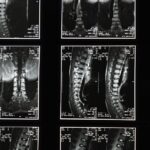

Quels examens sont nécessaires pour diagnostiquer la brachialgie?

Une IRM ou des radiographies sont souvent nécessaires pour confirmer la cause de la brachialgie.

Comment diagnostiquer correctement la brachialgie?

Un examen clinique, combiné à une imagerie médicale comme une IRM, est nécessaire pour un diagnostic précis.